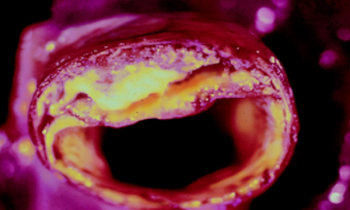

Si vos artères sont bouchées, sachez qu’il existe trois ingrédients efficaces qui peuvent améliorer, voire déboucher, les artères bouchées et éliminer la graisse du sang.